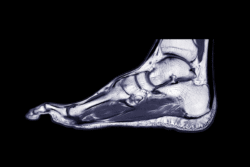

podiatry MRI vs. ultrasound: Which is right for your practice?

Are you struggling to decide between a podiatry MRI vs. ultrasound machine for your practice? This critical choice impacts patient care, workflow, and revenue. JayXray understands this complex equation. We empower you to make the most informed decision possible for your business. This guide will analyze the core considerations for each modality.

Purchasing an MRI machine represents a significant investment, but it offers unparalleled diagnostic capabilities. It provides superior contrast for complex soft tissue structures and excels at visualizing bone marrow. Practices specializing in sports medicine or complex trauma can handle cases they would otherwise outsource with an MRI. This not only keeps revenue in-house but also provides a comprehensive, multi-angle view for more accurate surgical planning. An in-office MRI can also attract a patient base with more advanced needs. JayXray knows that a thorough diagnostic tool is a powerful business asset.